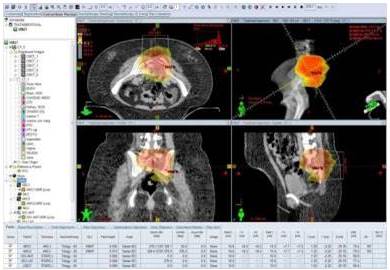

Se realiza simulación en posición prona con dispositivo de inmovilización tipo Belly-Board® que consiste en tablero con abertura central donde descansa el abdomen del paciente y condiciona un desplazamiento de las asas intestinales alejándolas del campo de irradiación. Se planifica radioterapia externa con técnica de arcos volumétricos modulados dirigidos a lesión en L5-S1 (Figura 3), con dos arcos con fotones de 6 MV a 200 cGy/día hasta 2 600 cGy en 13 aplicaciones desde el 21/5/14 al 6/6/14. Se evalúa la paciente en agosto de 2018 encontrándose sin síntomas ni alteraciones al examen físico, sin complicaciones, se realiza tomografía y resonancia con notable mejoría (Figura 4 y 5).